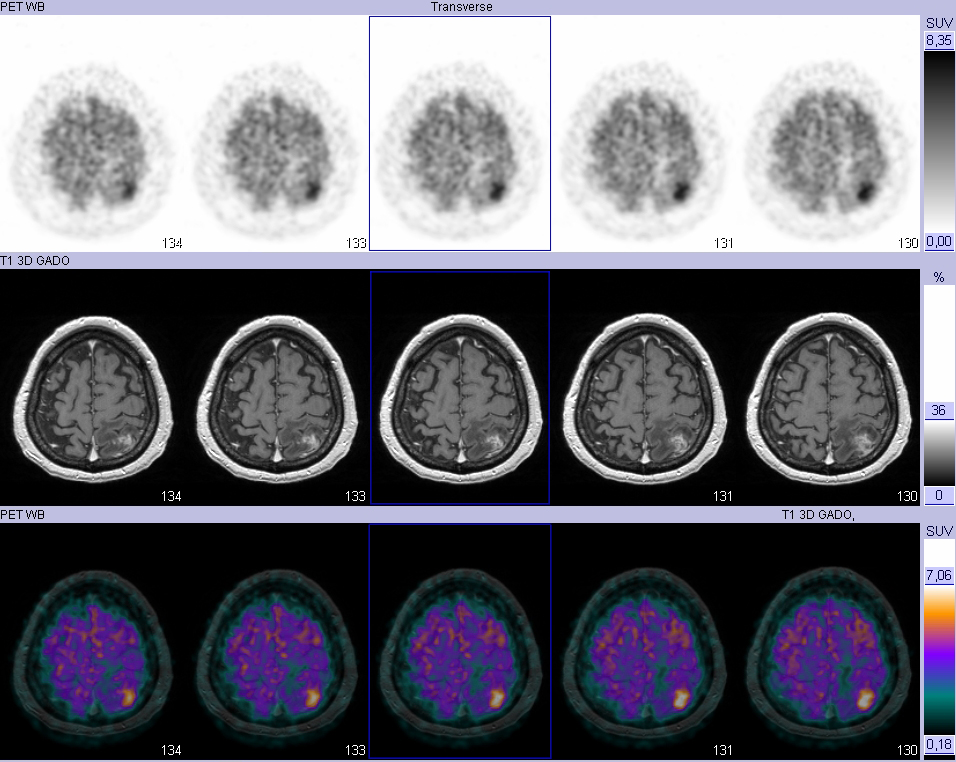

Homme de 60 ans, doute sur une radionécrose ou une récidive tumorale locale Images TEP tardives 4h après injection du FDG

Fusion avec les images IRM T1-Gado

Femme de 55 ans, doute sur une radionécrose ou une récidive tumorale locale Images TEP tardives 4h après injection du FDG

Hypométabolisme en regard de la lésion pari […]